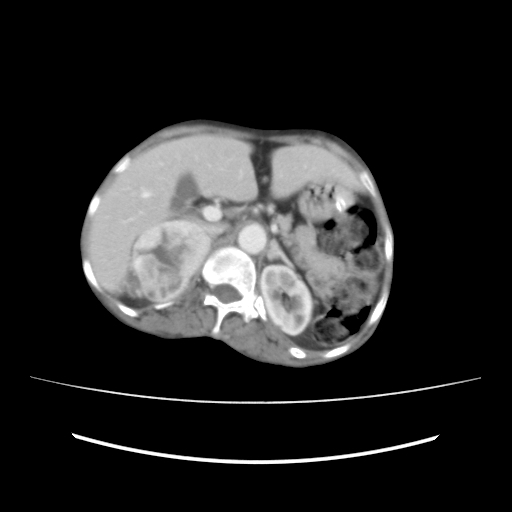

USG ABDOMEN

? Renal mass in the rt upper pole of kidney

? Adrenal mass

PLAIN CT - ABDOMEN

CECT abdomen

? CECT - MALIGNANT RIGHT ADRENAL MASS

CECT - Malignant right adrenal mass